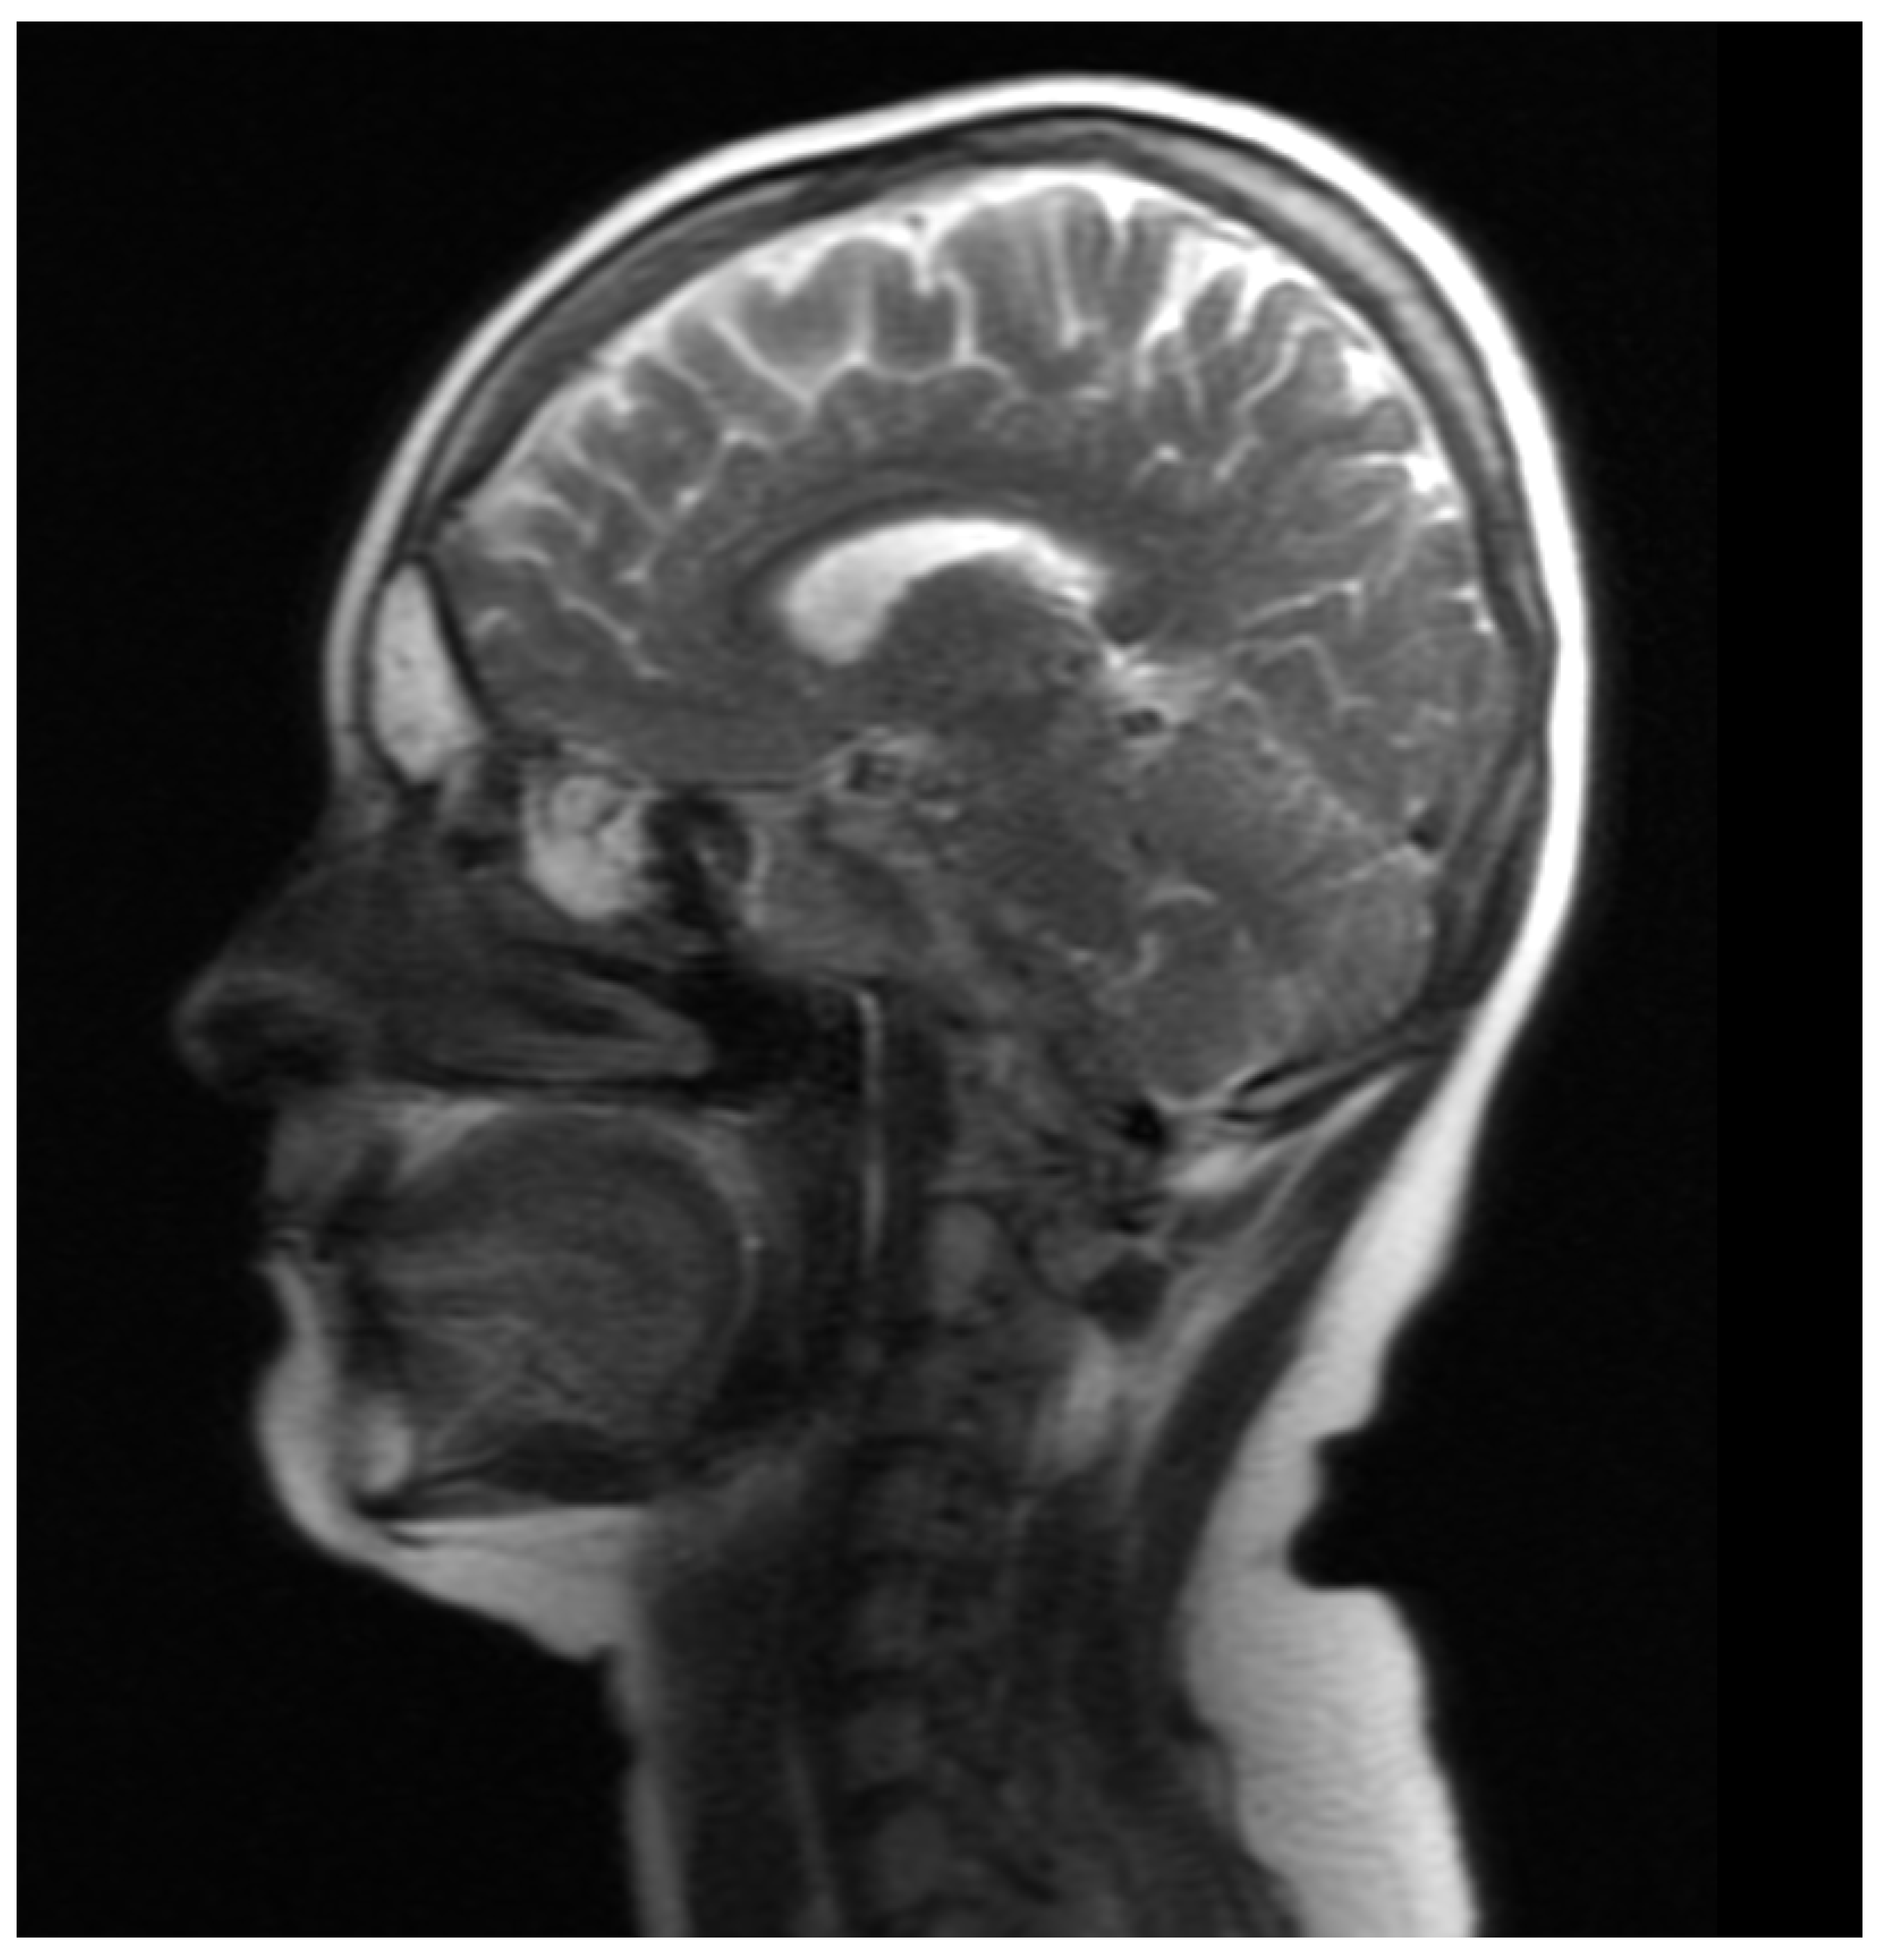

Figure 15. MRI of the head (sagittal plane) revealed frontal and ethmoid sinus involvement.

In March 2022, during another hospitalization, laboratory tests revealed the following: an erythrocyte sedimentation rate of 15 mm after 1 h, CRP 2.3 mg/dL, normal liver and kidney function parameters, slight neutrophilic leukocytosis (secondary to steroid therapy), IgA, IgG, and IgM within normal limits. Chest X-ray was positive for single-banded changes in the inferior lobe of the right lung. Apart from those findings, the X-ray results were unremarkable. However, head MR showed smooth thickening of the brain dura mater, revealing new inflammatory lesions in the frontal sinuses (Figure 14 and Figure 15).

Treatment with RTX was reintroduced. Cyclosporine dose was increased to 200 mg/day and methotrexate up to 30 mg/week. After the RTX therapy course, the ocular assessment revealed a quiet eye with left compressive optic neuropathy (a pale disc with RNFL atrophy) and bilateral posterior subcapsular cataracts (Figure 16). The final visual acuity was logMar 0.0 in the RE and light perception in the LE.